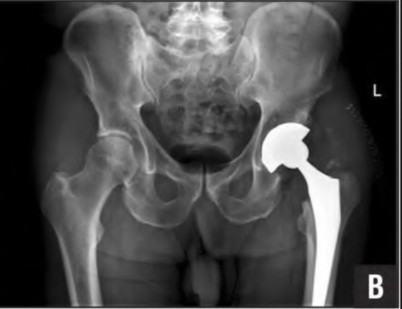

A 72-year-old male presents 2 years status post fixation of an impending pathologic right femur fracture due to metastatic renal cell carcinoma. He is minimally ambulatory due to pain. Despite radiation therapy, there has been progression of the lesion with extensive cortical bone loss, which is shown in Figure A. A proximal femoral replacement arthroplasty is performed without complications, and is demonstrated in Figure B. Which of the following is true regarding this patients post-operative course?

Deep prosthetic infection is the most common complication after hip arthroplasty performed for salvage of failed internal fixation after pathologic proximal femoral fracture secondary to malignancy.

Jacofsky et al reviewed the complications in 42 patients with a mean age of 63 who were treated with hip arthroplasty for salvage of failed treatment of a pathologic proximal femoral fracture. Multiple different constructs were used.

The most common complication was deep prosthetic infection, which occurred in nearly 10% of the patients studied. All infections occured in patients whom had previously received radiation. The mean Harris Hip score improved from 42 to 83 points post-operatively, and 41 of the 42 patients were ambulatory at follow-up. Implant survivorship free of revision for any reason at 5 years was 90%, and free of revision for aseptic failure or radiographic failure was 97%.

Figure A shows a lytic lesion of the proximal femur with an intramedullary implant. Figure B shows a proximal femoral replacement.